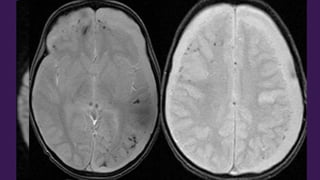

Este documento presenta el caso de un niño de 3 años que sufrió episodios de paresia y alteraciones neurológicas. Exámenes revelaron la presencia de un higroma cerebral que fue drenado. A pesar de una mejoría inicial, el niño continuó presentando síntomas neurológicos intermitentes. Exámenes posteriores identificaron una rara vasculopatía que afecta vasos cerebrales y otros órganos, con un pronóstico grave.